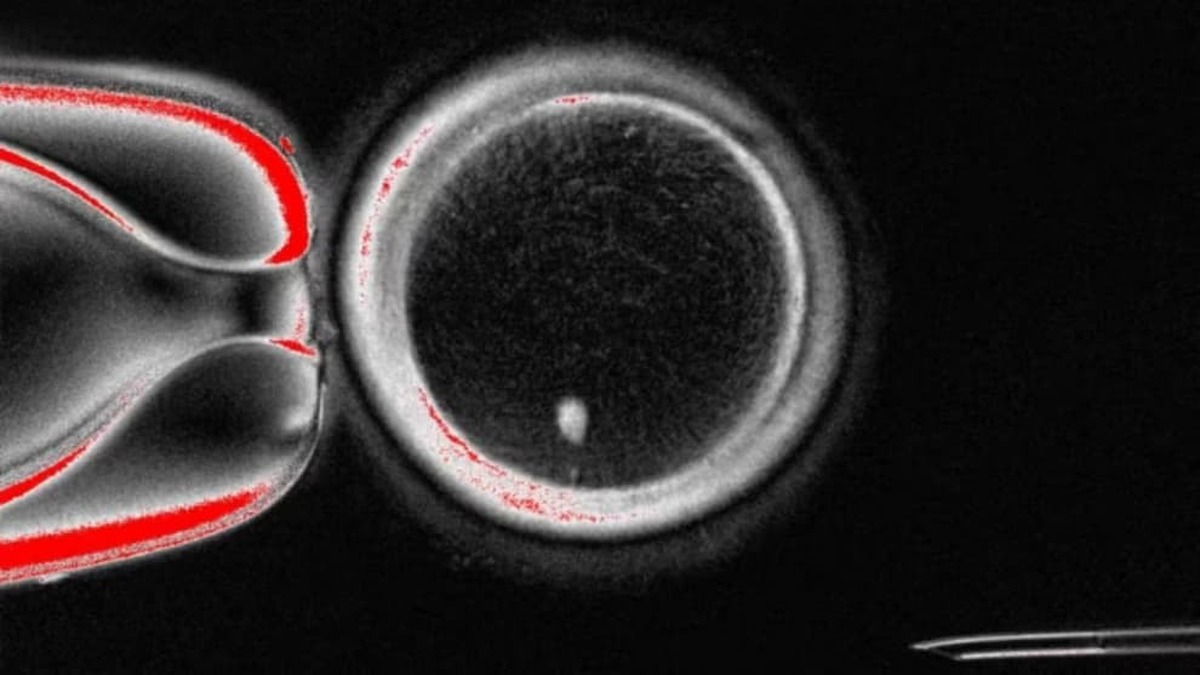

به گزارش مجله خبری نگار، دانشمندان دانشگاه علوم پزشکی و سلامت اورِگان (OHSU) موفق شدند با بهره‌گیری از فناوری کلونینگ، از سلول‌های پوستی و تخمک‌های اهدایی، تخمک انسانی تولید کنند. این دستاورد می‌تواند امیدی تازه برای زنان نابارور و حتی زوج‌های همجنس‌گرا ایجاد کند تا صاحب فرزندانی با ارتباط ژنتیکی شوند. با این حال، متخصصان تاکید دارند که ورود این روش به مرحله درمانی دست‌کم ۱۰ سال زمان خواهد برد.

در این پژوهش، هسته سلول‌های بالغ به تخمک‌های اهدایی که هسته‌شان حذف شده بود منتقل شد. DNA واردشده در یک فرآیند خاص، سلول‌ها را مجبور کرد نیمی از کروموزوم‌های خود را کنار بگذارند. این بازآرایی، مرحله‌ای حیاتی برای آمادگی تخمک جهت لقاح محسوب می‌شود.

در این پژوهش ۸۲ تخمک تولید شد که با روش لقاح آزمایشگاهی (IVF) بارور شدند. اما تنها ۹ درصد از آنها توانستند به مرحله بلاستوسیست برسند، در حالی‌که در شرایط طبیعی این رقم حدود یک‌سوم است. هیچ‌یک از جنین‌ها پس از این مرحله پرورش داده نشدند.